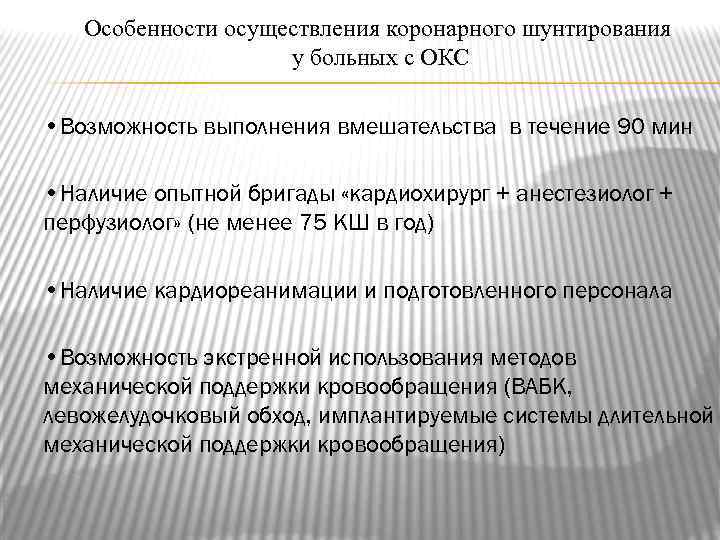

Особенности осуществления коронарного шунтирования у больных с ОКС • Возможность выполнения вмешательства в течение 90 мин • Наличие опытной бригады «кардиохирург + анестезиолог + перфузиолог» (не менее 75 КШ в год) • Наличие кардиореанимации и подготовленного персонала • Возможность экстренной использования методов механической поддержки кровообращения (ВАБК, левожелудочковый обход, имплантируемые системы длительной механической поддержки кровообращения)

Особенности осуществления коронарного шунтирования у больных с ОКС • Возможность выполнения вмешательства в течение 90 мин • Наличие опытной бригады «кардиохирург + анестезиолог + перфузиолог» (не менее 75 КШ в год) • Наличие кардиореанимации и подготовленного персонала • Возможность экстренной использования методов механической поддержки кровообращения (ВАБК, левожелудочковый обход, имплантируемые системы длительной механической поддержки кровообращения)